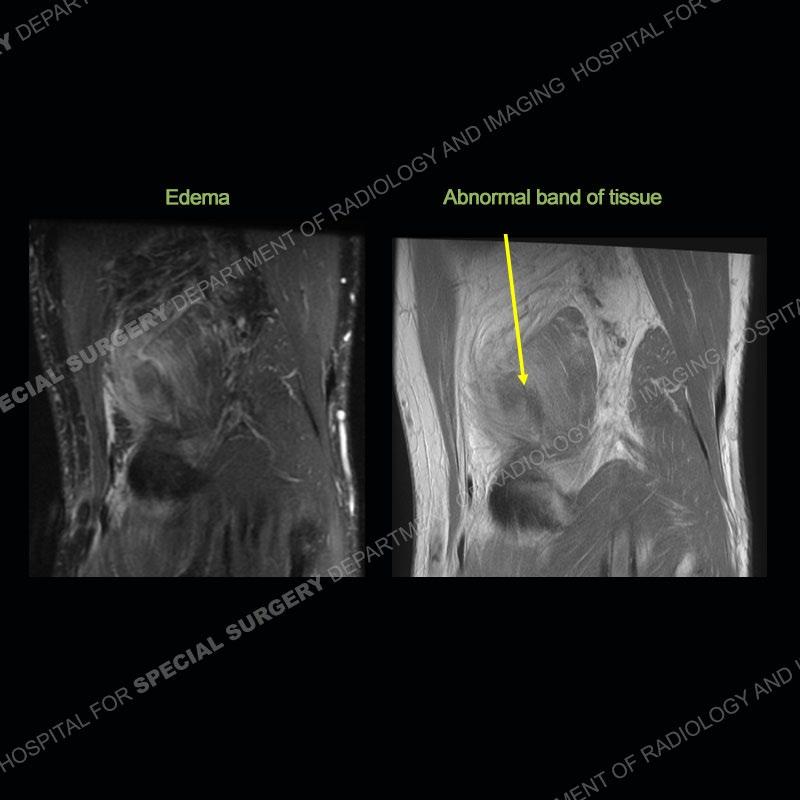

The radiographs show degenerative change of the medial compartment and a varus knee, but they are not germane to this case. No acute bony injury is present. The MRI shows edema of the posterior medial knee/soft tissue and a focal area of a partially disrupted low signal structure. The details are kept at a minimum in the findings of this case on purpose.

Diagnosis: Partial Disruption Medial Head Gastrocnemius (MHG)

Fourth, use all imaging planes and different pulse sequences to make your diagnosis. The edema highlighted in this case can be seen as the obscuration of fat on the PD images but is much easier to perceive as the high signal on the IR pulse sequences. The actual disruption of the MHG myotendinous junction is only able to be seen on the axial images. On the sagittal and coronal images, we get a sense something is wrong but hard to be exact. Lastly, when you look at a study and something just seems off (as I would say the sagittal and coronal images do with that dark band of tissue posteriorly), listen to yourself and go through the study slowly and meticulously. Most of the time you will find you were right, and something indeed is present.